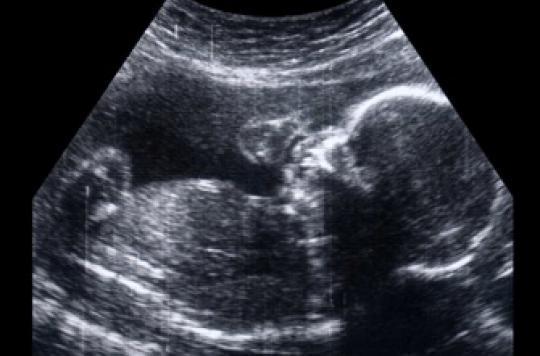

Savoir le sex du bebe echographie

Savoir le sex du bebe echographie-1 Test des mainsTout le monde ira de ses prédictions Pourtant, ce n'est que l' échographie qui vous révélera ce grand secret En attendant ce jour, voici 15 trucs pour prédire le sexe de bébé Attention!

Mais prudence, tout dépend du moment où l'échographie est réalisée et du temps que le praticien prend pour examiner le sexe Sachant que la première échographie a un objectif bien défini (nombre de fœtus et localisation, vitalité du fœtus, clarté nucale , anatomie), l'identification du sexe n'est clairement pas la prioritéCette façon de faire estelle fiable ?Fille ou garçon comment savoir ?

J'ai récemment écrit un article sur les différentes stratégies pour connaître le sexe du bébé dans le ventre de sa maman et si tu as été assidue, tu auras retenu que tu ne pourras être fixée qu'à partir de la deuxième échographie obligatoire, celle que tu fais au cours du 5ème mois de grossesse Cela dit, « 5 mois, c'est loooong !Comment savoir si on est enceinte d'une fille ou d'un garçon?Que des histoires de grandsmères et des mythes étranges, mais de quoi passer le temps avant le grand jour!